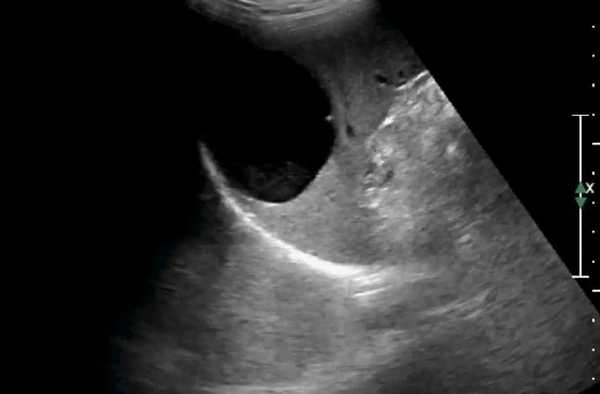

Кисты в селезенке на ультразвуковом сканировании, которые иногда обнаруживаются, могут быть истинными или псевдокистами. Если киста обнаружена, то, как правило, бывает трудно определить начальную этиологию, но ее стенки должны быть тщательно изучены, чтобы помочь определить, является ли это первичная врожденная киста или киста от вторичного инфекционного процесса или гематомы, в последнем случае она не будет иметь эпителиальную выстилку. Однако, как правило, невозможно, различить истинные и псевдокисты. Селезеночные кисты могут разрываться или воспаляться. Эпидермоидная киста также может возникнуть в селезенке, и тогда она проявляется, как и другие кистозные образования. В кисте или в ее стенке могут быть кальцинаты и она может содержать внутренние септы. На УЗИ селезенки киста может появиться с комплексным содержимым в результате кровоизлияний или инфекции. Инфекционный эхинококкоз может также рассматриваться в селезенке, как результат от разрыва кисты печени или системного разноса инфекции. Они будут хорошо с определяемыми границами, одиночными или множественными, с кальцифицированными стенками.

Ультразвуковая картина, как и при любой острой гематоме, по внешнему виду от свежей крови может быть гиперэхогенной и ее бывает трудно отличить от обычной селезенки. Когда гематома начинает разжижаться, то в центре она становится гипоэхогенной и ее легче обнаружить. Наконец, после того, как она организовалась, то может выглядеть как линейные гиперэхогенные включения или при лизисе стать кистозной. Субкапсулярная жидкость видно только под капсулой селезенки, которая обычно видна в форме полумесяца. Если произошел разрыв селезенки тогда жидкость может быть видна во фланке или в остальной части брюшной полости.